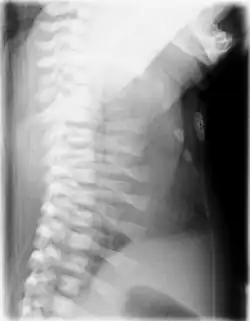

Die Asphyxierende Thoraxdysplasie ist eine sehr seltene angeborene Skelettdysplasie aus der Gruppe der Kurzripp-Polydaktylie-Syndrome mit sehr kurzen Rippen und entsprechend schmalem Thorax, kurzen Gliedmaßen und typischen Veränderungen im Röntgenbild. Sie zählt zu den Ziliopathien und verläuft häufig letal.[1][2][3] Die Erkrankung kann als Subtyp des Joubert-Syndromes (Joubert-Syndrom und verwandte Krankheiten) angesehen werden.[4]

Der Ausprägungsgrad der Veränderungen kann beträchtlich unterschiedlich sein. Klinische Kriterien sind:[1][2] Thoraxdeformität mit langem, schmalen Thorax mit Atemnot des Neugeborenen infolge Platzmangels für die Lunge; Kurze Extremitäten mit Kleinwuchs, eventuell Polydaktylie; Im späteren Kindesalter können Niereninsuffizienz, Retinopathie, Fibrosierung von Leber und Pankreas auftreten.

Die klinische Verdachtsdiagnose wird im Röntgenbild gesichert. Diagnostische Kriterien sind:[1][2][14]

- Kurze, horizontal verlaufende Rippen

- Schmale Beckenschaufeln mit dreizackartiger Begrenzung des Unterrandes, Pfannendach horizontal verlaufend und spornartig nach kaudal weisend